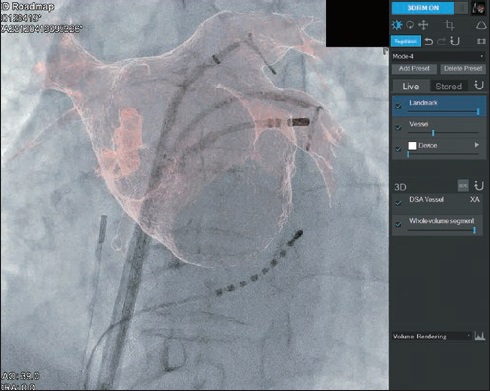

Програмне забезпечення MM Roadmap

3D об’єм, отриманий з КТ або МРТ (будь-якого виробника мед.обладнання) та скопічне зображення можуть бути автоматично (або вручну) накладені та виведені на монітор. Зображення на моніторі змінюватиметься синхронно в залежності від нахилу С-арки, зміни SID, поля огляду, висоти та положення деки столу.